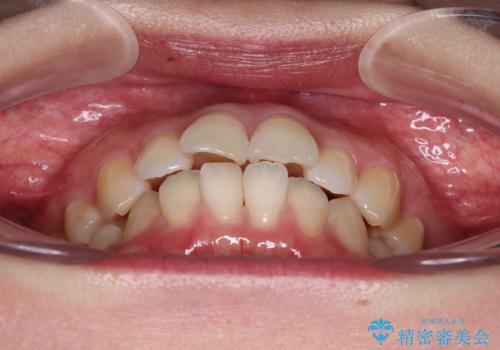

- 上下前歯の後戻りを気にして来院された患者様です。

インビザラインでの治療を希望されていて、デコボコの程度が中等度であり、安価なパッケージにて対応可能と判断されたため、インビザライン・モデレートを用いて矯正治療を行うこととしました。